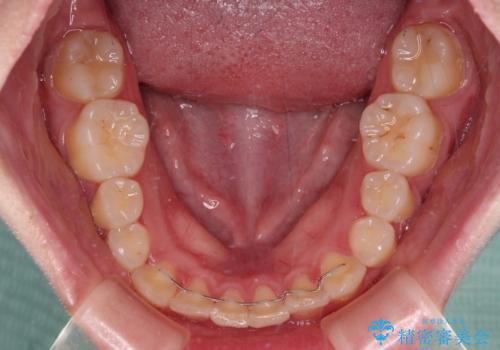

- 治療期間

- 5年1ヶ月

- 矯正治療後の保定が不十分だと後戻り(元の位置に戻ろうとする動き)をします